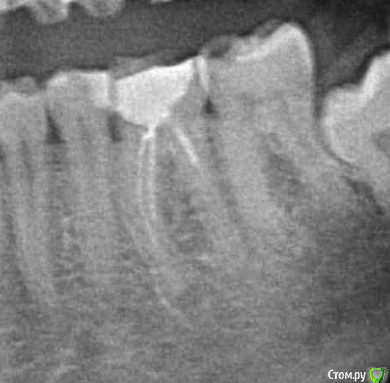

alex2016 Опубликовано 23 апреля, 2016 Поделиться Опубликовано 23 апреля, 2016 Добрый день, Сегодня был у стоматолога в профилактических целях. Т.к. нахожусь в США, то насчитали на ремонт 2600$ (учитывая страховку), т.к. 2600 тратить не сильно горю желанием хочу посоветоваться. Вопрос #1. В одном из зубов (его назвали №19 вроде как, снимок 1) врач обнаружил абсцесс. В этом зубе делали депульпирование и врач сказал, что депульпирование было сделано не до конца и на снимке это видно, т.е. они хотят заново вскрывать канал и заливать его (оба). К тому же он сказал, что в канале застрял кончик сверла (тут не уверен что это называется именно сверло) и его придётся доставать, возможно со стороны десны, если традиционным методом сделать это не получится. Абцесс он мне показал на снимке как небольшое затемнение на челюсти. Зуб не болит и кроме того, что между ним застряёт еда и он сам выглядит не презентабельно ничем не мешает, врач предлагает ставить коронку. Насчёт коронки возражений нету, т.к. еда застряёт и зуб выглядит не презентабельно, хотя в глаза это не бросается т.к. это моляр, а вот насчёт абсцесса я бы хотел уточнить здесь и получить второе мнение. Вопрос #2. Доктор предлагает поставить коронку на зубе #30, картинка #2. Хотя на зубе и достаточно большая пломба, он не выглядит не презентабельно и абсолютно не беспокоит, конечно, он выглядит чуть хуже обычного зуба, но гораздо лучше зуба #1. Сам я склоняюсь к тому, что пока с этим зубом делать ничег не нужно, но второе мнение хотелось бы всё-таки выслушать. Вопрос #3. Доктор предлагает удалить верхние зубы мудрости, т.к. они оказывают давление на дёсны или ещё куда-то там. Здесь я склоняюсь к тому, что он может быть прав насчёт верхнего зуба, потому что у меня там периодически застряёт еда между десной и самим зубом и вызывает неприятные ощущения, правый верхний зуб мудрости абсолютно никаких негативных ощущений не вызывает. Есть ли возможность избавиться от застрявания еды между зубом и десной (это происходит сзади-справа) без удаления зуба? Можно ли удалять один зуб мудрости, а не оба? Вопрос #4. У меня не правильный прикус из-за которого сточились передние верхние зубы, доктор предлагает удалить два верхних зуба, которые идут за клыками, подтянуть верхние передние зубы вперёд и поставить на них коронки, чтобы вернуть хороший прикус и эстетику (сейчас при закрытом рте расстояние между передними зубами верхней челюсти и нижней примерно в 1см). Вся эта процедура займёт кучу времени, т.к. придётся ставить брекет систему и удалять зубы. В клинике в Киеве мне тоже предлагали такой вариант. Зубы хочу сделать, чтобы улыбка стала красивее, поэтому вопросы: А. Обязательно ли удалять 2 зуба для этой процедуры?Б. Если удалить два верхних зуба мудрости, не отодвинутся ли зубы назад сами по себе?В. Хороший ли вариант ставить коронки на абсолютно здоровые, но немного сточенные зубы дли улучшения эстетики? Возможно зубы можно просто нарастить?Г. Не повлияет ли удаление двух зубов на положение верхней губы? При закрытом рте отклонений в прикусе особо не заметно. Благодарю за ответы. Ссылка на комментарий

DmitrySH Опубликовано 23 апреля, 2016 Поделиться Опубликовано 23 апреля, 2016 Вопрос 1.Да, ревизия каналов нужна, коронка нужна, инструмента не увидел на снимке, самое интересное срезано.. нужен снимок еще как минимум 5 мм ниже. Ссылка на комментарий

alex2016 Опубликовано 23 апреля, 2016 Автор Поделиться Опубликовано 23 апреля, 2016 (изменено) Вопрос 1.Да, ревизия каналов нужна, коронка нужна, инструмента не увидел на снимке, самое интересное срезано.. нужен снимок еще как минимум 5 мм ниже.Вот сделал скриншот с другой фотографии. Качество какое есть, если нужно могу спросить нет ли у них качества получше, такое впечатление что отсканировали в самом плохом качестве, т.к. то что они мне показывали выглядело более детализировано. вопрос 2.Может быть не коронку, но керамический оверлей очень кстати, и вкладку или пломбу на 5ый зуб перед ним и 5ый над ним.Благодарю. Доктор, почему-то не упоминал об этой возможности, рассказывал только про импланты и коронки. Уточню насчёт этого. 3 вопрос, скорее всего да, но не по снимку об этом рассуждатьДа в плане того, что можно удалять только один зуб, или то, что можно избавиться от проблемы без удаления зуба? Зуб не болит абсолютно и я даже не знал о том, что это зуб мудрости, просто когда я ем орехи или морковку и они попадают между десной и зубом, то десна воспаляется и вызывает неприятные ощущения, вот сейчас абсолютно нормально и зуб не достаёт совсем, но когда доктор смотрел этот зуб я отчётливо понял, что это именно то место, потому что он его немного зацепил своим прибором, т.е. какая-то проблема там есть, но неужели такая мелочь решается только методом удаления зуба? Изменено 23 апреля, 2016 пользователем alex2016 Ссылка на комментарий

DmitrySH Опубликовано 23 апреля, 2016 Поделиться Опубликовано 23 апреля, 2016 По таком снимку тоже наличие/отсутствие инородного тела в канале сложно определить, но факт что требуется лечение.Ваши верхние восьмые зубы не используются по назначению. Можете смело удалять, в функциональном аспекте ничего не потеряете. 1 Ссылка на комментарий